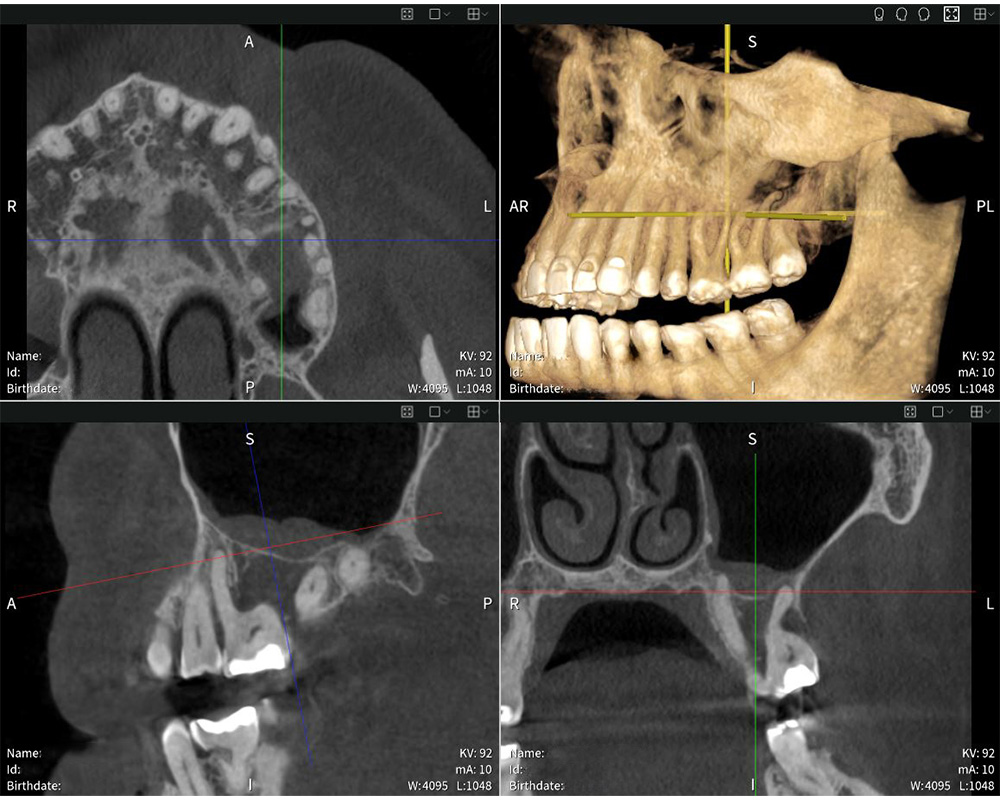

Highly precise imaging results with Seethrough Max: the X-ray shows the swelling of the mucosa in the sinus maxillaris.

Highly precise imaging results with Seethrough Max: the X-ray shows the swelling of the mucosa in the sinus maxillaris. © Dr med. dent. Mauro Amato